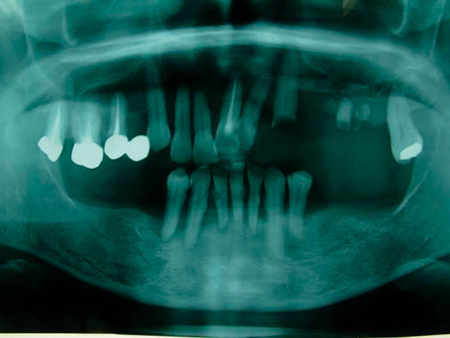

40代男性。右上と左下の歯が喪失して、そのままになっている。

左上と右下の歯は治療途中で崩壊しており、このまま治療中断を繰り返せば歯を喪失することが予想される。